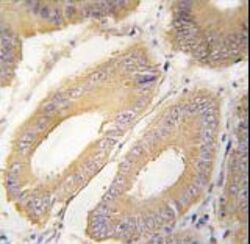

- Formalin-fixed and paraffin-embedded human colon carcinoma tissue reacted with FGF4 Antibody , which was peroxidase-conjugated to the secondary antibody, followed by DAB staining. This data demonstrates the use of this antibody for immunohistochemistry; clinical relevance has not been evaluated.

- Formalin-fixed and paraffin-embedded human colon carcinoma tissue reacted with FGF4 Antibody , which was peroxidase-conjugated to the secondary antibody, followed by DAB staining. This data demonstrates the use of this antibody for immunohistochemistry; clinical relevance has not been evaluated.

- Formalin-fixed and paraffin-embedded human colon carcinoma tissue reacted with FGF4 Antibody , which was peroxidase-conjugated to the secondary antibody, followed by DAB staining. This data demonstrates the use of this antibody for immunohistochemistry; clinical relevance has not been evaluated.